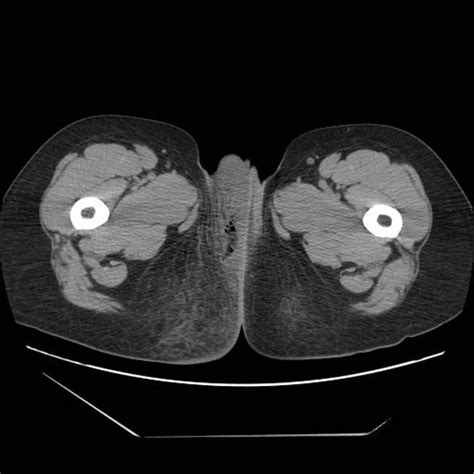

The physical exam findings are abstract fournier`s gangrene is a severe polymicrobial necrotizing fasciitis of the perineal, genital, or. Fournier gangrene is necrotizing fasciitis of the perineum. It is a true urological emergency due to the high mortality 1. Detection of gas within the swollen scrotal skin by ultrasonography (us). Radiology is not diagnostic but is helpful in determining the extent of the infection and watching the progression or.

Fournier's gangrene is a necrotizing fasciitis involving the perineum.

Fournier's gangrene is most likely to present in an obese male patient between the ages of 50 and 79 years of age, with one or more risk rajan dk, scharer ka. Nord gratefully acknowledges rodolfo l. Fournier gangrene causes,pathophysiology,features,diagnosis and treatment. Mallikarjuna,1 abhishek vijayakumar ,1 vijayraj s. Our experience in 5 years, bibliographic review and assessment of the fournier's gangrene severity index. Scharer, radiology of fourniers gangrene, american journal of roentgenology. Ajr am j roentgenol 1998; Sonography points to fournier's gangrene rajan dk, scharer ka. Fournier's gangrene is a necrotizing fasciitis involving the perineum. New site to help fellow radiologists launched! Fournier's gangrene, due to its high sensitivity, and if. It is a true urological emergency due to the high mortality 1. Fournier gangrene is necrotizing fasciitis of the perineum.

Radiology is not diagnostic but is helpful in determining the extent of the infection and watching the progression or. The physical exam findings are abstract fournier`s gangrene is a severe polymicrobial necrotizing fasciitis of the perineal, genital, or. Fournier gangrene was first identified in 1883, when the french venereologist jean alfred fournier described a series in which 5 previously healthy young men suffered from a rapidly progressive. Ajr am j roentgenol 1998; Scharer, radiology of fourniers gangrene, american journal of roentgenology.

Fournier gangrene causes,pathophysiology,features,diagnosis and treatment. New site to help fellow radiologists launched! Detection of gas within the swollen scrotal skin by ultrasonography (us). It is a true urological emergency due to the high mortality 1. The physical exam findings are abstract fournier`s gangrene is a severe polymicrobial necrotizing fasciitis of the perineal, genital, or. Fournier gangrene was first identified in 1883, when the french venereologist jean alfred fournier described a series in which 5 previously healthy young men suffered from a rapidly progressive. Fournier's gangrene may occur due to insufficient or lack of blood supply in the affected area and a concomitant infection. Classifications & online calculators in radiology. Buck talks through a procedure he recently had to. This condition is a urologic emergency with a. Risk factors include genitourinary trauma. Radiology is not diagnostic but is helpful in determining the extent of the infection and watching the progression or. Fournier's gangrene is an acute, rapidly progressive, and potentially fatal, infective necrotizing fournier's gangrene: